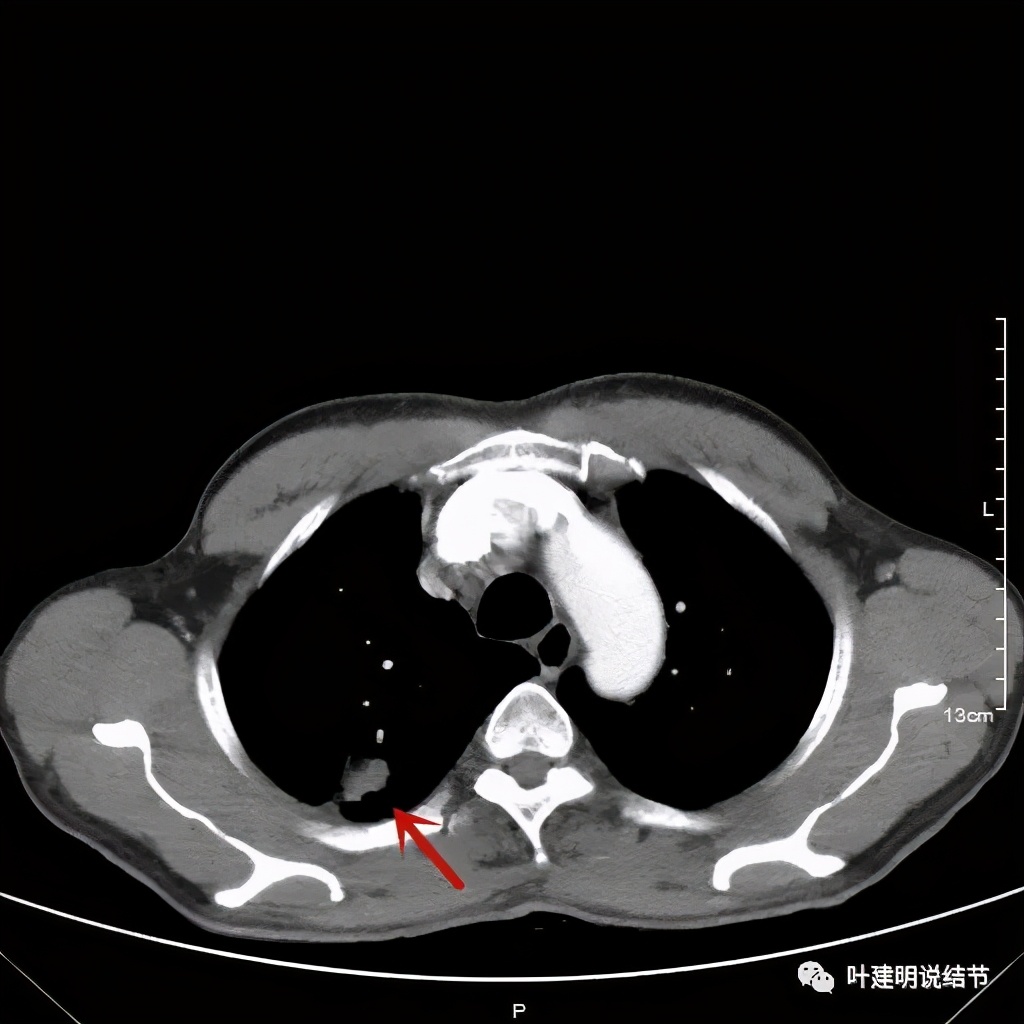

以上诸图是纵隔窗

总体上感觉,病灶比较大,不规则,不是圆形或圆形生长,周围有模糊磨玻璃影(考虑炎性渗出性?),虽有胸膜牵拉,但力度不够;增强有显著强化。病灶明显却无明显临床症状,普通感染是不像的,要么是结核,要么是肺癌。但肺癌的话,在2年前没有,2年内长到这么大,恶性程度应该很高,但其纵隔淋巴结却没有明显肿大。而且病灶的边缘部分过于光滑,没有见到肿瘤的细毛刺,膨胀性也不够。整体看病灶有点像“腰子”形,弯弯曲曲的。所以我的感觉更倾向结核性。查了肿瘤筛查指标如下: